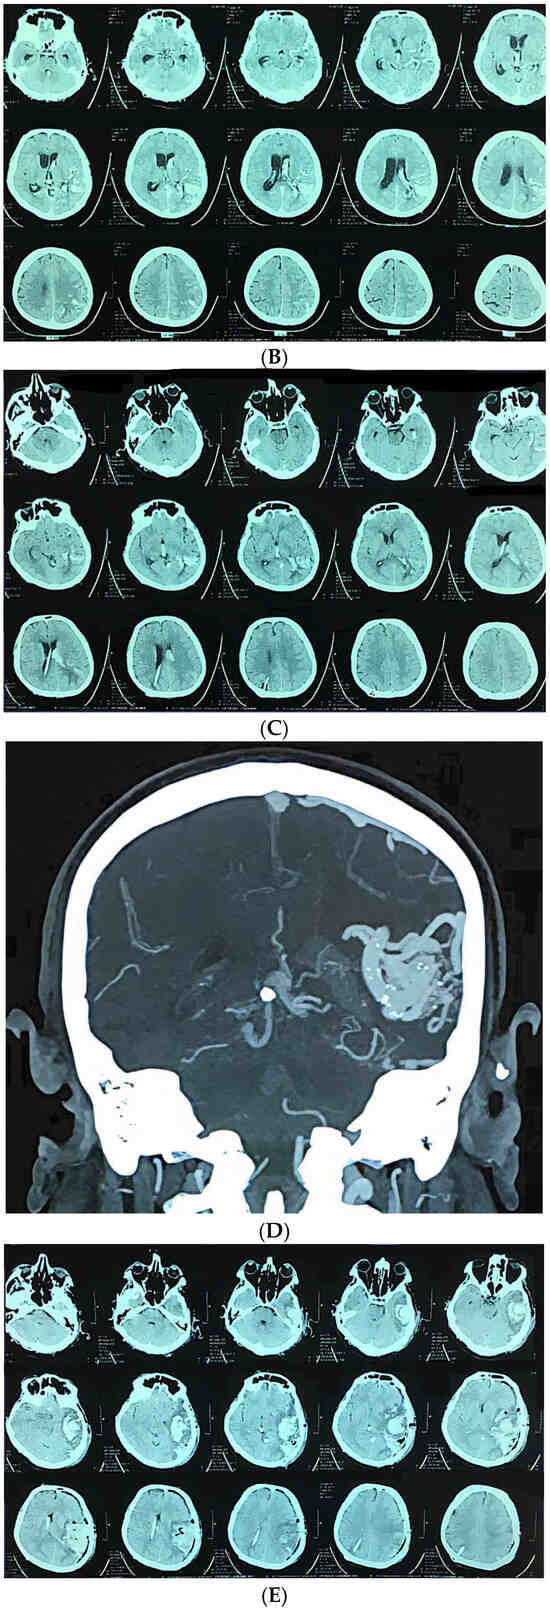

Microsurgical Resection of Unruptured Brain Arteriovenous Malformations: A 12-Year Single-Center Experience

Background and Objectives: The management of unruptured brain arteriovenous malformations (ubAVMs) remains controversial, particularly following the ARUBA trial, which favored conservative management. However, concerns regarding the validity of its findings persist. This study aimed to evaluate the outcomes of microsurgical resection of [...] Read more.

Background and Objectives: The management of unruptured brain arteriovenous malformations (ubAVMs) remains controversial, particularly following the ARUBA trial, which favored conservative management. However, concerns regarding the validity of its findings persist. This study aimed to evaluate the outcomes of microsurgical resection of ubAVMs in a high-volume neurosurgical center. Materials and Methods: This is a retrospective single-center study that analyzed 52 patients treated by microsurgical resection at the Cerebrovascular Department, University Clinical Center of Serbia, between January 2010 and January 2022. All patients were classified according to the supplementary Spetzler–Martin (suppl-SM) grading system and stratified into low-risk (suppl-SM ≤ 6) and high-risk (suppl-SM > 6) groups. Functional outcomes were assessed using the modified Rankin Scale (mRS) at discharge and 9-month follow-up. Results: The mean patient age was 38.8 years, with equal gender distribution. Epileptic seizure was the most common presenting symptom (80.4%). In the low-risk group, there were no deaths, and poor outcomes were rare (6.8% at discharge; 2.3% at 9 months). Conversely, the high-risk group demonstrated significantly worse outcomes (62.5% poor outcome at discharge, 28.6% at 9 months). The overall hemorrhagic stroke rate was 5.8%, with one fatality (12.5%) in the high-risk subgroup. Absence of superficial venous drainage and presence of combined/deep venous drainage were strongly associated with poor outcomes. Conclusions: Microsurgical resection of ubAVMs is a safe and effective treatment strategy for low-grade lesions, yielding excellent functional outcomes and minimal morbidity. Our findings, supported by other large series, reinforce microsurgery as the gold standard for low-grade ubAVMs in appropriately selected patients. Full article